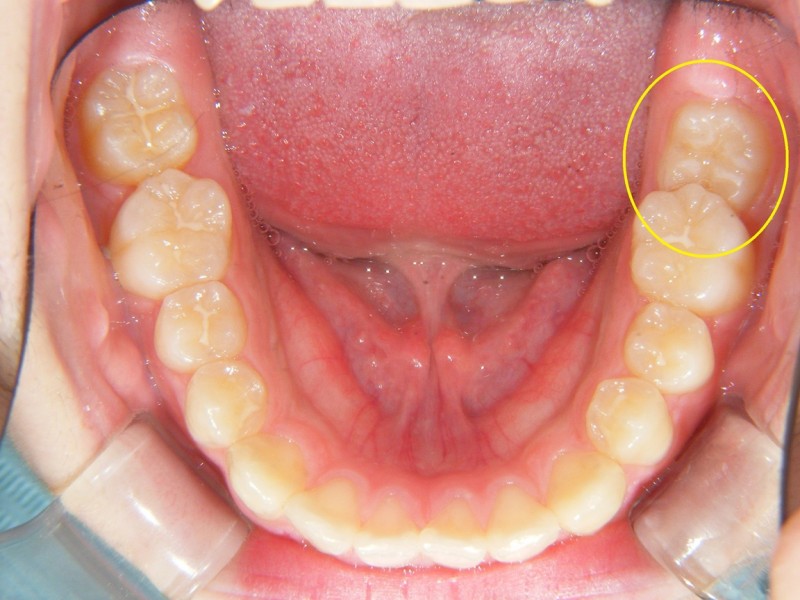

中学生の部分矯正のケースをアップします。

↑左下一番奥の歯(第二大臼歯)が、ひとつ前の歯(第一大臼歯)に引っかかって、萌出できない状態になっています。放置すると、引っかかったままの状態になります。親知らずが成長してくると、治すのも難しくなっていきます。

このようなケース、結構見かけます。